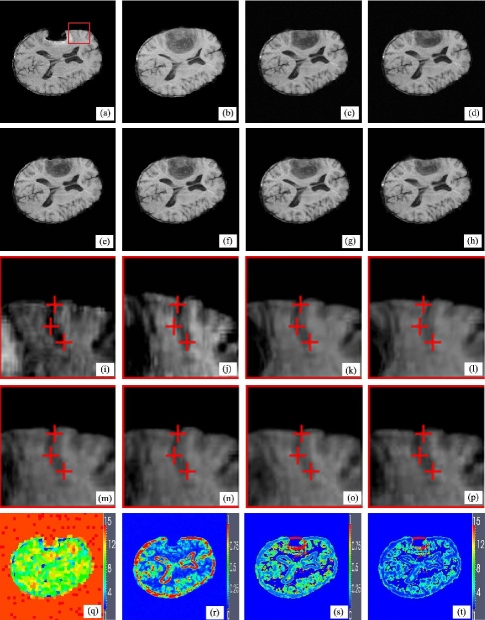

Figure 3: Brain tumor resection image registration. (a)-(b) The reference and moving images, (c) the proposed method, (d) the previous method, (e) AMI, (f) AMM, (g) DDD, (h) BMI, (i)-(p) the same sulcus in (a)-(h) with desired spatial positions located by red cross, (q) structure scale map, (r) JSM, (s) mismatch scale map, (t) kernel scale map.

The first experiment involves matching pre- and post-operative brain tumor resection images. Brain tissue severely suppressed by tumor in the preoperative image (Fig. 3(a)(b)) expands after tumor resection, which introduces not only the missing correspondence of tumor in the post-operative images but also the local large deformations caused by the brain shift. Fig. 3(c)-(h) are the registered results of the proposed method, the previous method, AMI, AMM, DDD and BMI. Visual inspection has revealed that the proposed method, the previous method, AMI and AMM methods apparently perform better than the DDD and BMI methods because the local brain deformation resulted from the latter two methods is either insufficient or somewhat excessive. The deformations of the sulcus near the missing corresponding tumor region in Fig. 3(a)-(h) are emphatically illustrated in Fig. 3(i)-(p). Comparing Fig. 3(k) with Fig.3(l) shows the improvement of the proposed method to the previous method in registration accuracy. The structure scale map, JSM, mismatch scale map and kernel scale maps at the finest resolution of the images for the proposed method are shown in Fig. 3(q)-(t).